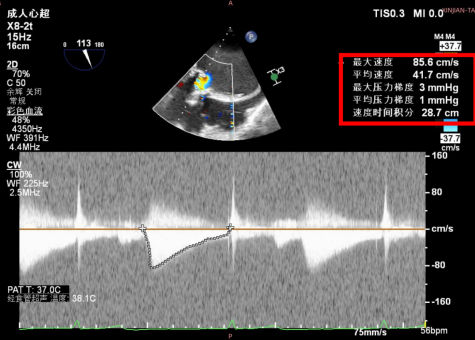

康复大学青岛中心医院林明山教授分享一例“双瓣一站式”高难度VIV病例,深刻展现自膨短瓣在生物瓣衰败VIV中的应用价值。患者83岁男性,于2010年行主动脉瓣置换术、二尖瓣置换术及三尖瓣成形术,现主动脉瓣和二尖瓣生物瓣均出现重度反流,术前超声/CT充分评估后,决定采用经心尖入路,先行主动脉瓣瓣中瓣植入术(TAVR-VIV),顺利送入ScienCrown TAVTA 23mm瓣膜,得益于该款瓣膜短瓣架设计,完全释放后对血流影响小,因此TAVR-VIV术中无需起搏,瓣膜初次释放位置稍浅,部分回收调整瓣膜深度重新释放,即刻造影示瓣膜位置良好,无张力脱钩瓣膜位置稳定,术后TEE示主动脉瓣平均跨瓣压差仅4mmHg。随后行二尖瓣瓣中瓣植入术(TMVR-VIV),经心尖入路植入ScienCrown TAVTF 29mm瓣膜,主动脉根部造影,冠脉显影良好无瓣周漏,术后TEE示二尖瓣平均跨瓣压差仅1mmHg。

TAVR-VIV术后TEE

TMVR-VIV术后TEE